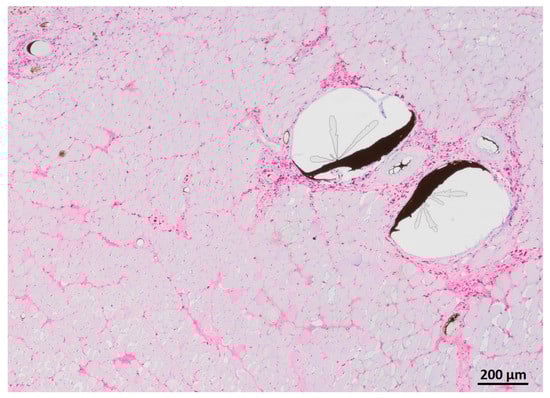

3.5. Myofiber Morphology and Macrophage Invasion

HE staining showed partly well-preserved structures as well as partly inhomogenous and irregularly arrangement of the skeletal muscle similar to MHC staining (Figure 11). CD68 staining revealed invasion of macrophages, especially near the vessels (Figure 12).

Figure 11. HE staining of the transplanted muscle showing partly well-preserved structures as well as partly inhomogenous and irregularly arrangement of the skeletal muscle.

Figure 12. CD68 staining of transplanted muscle showing macrophages predominantly near the vessels filled with Microfil®.